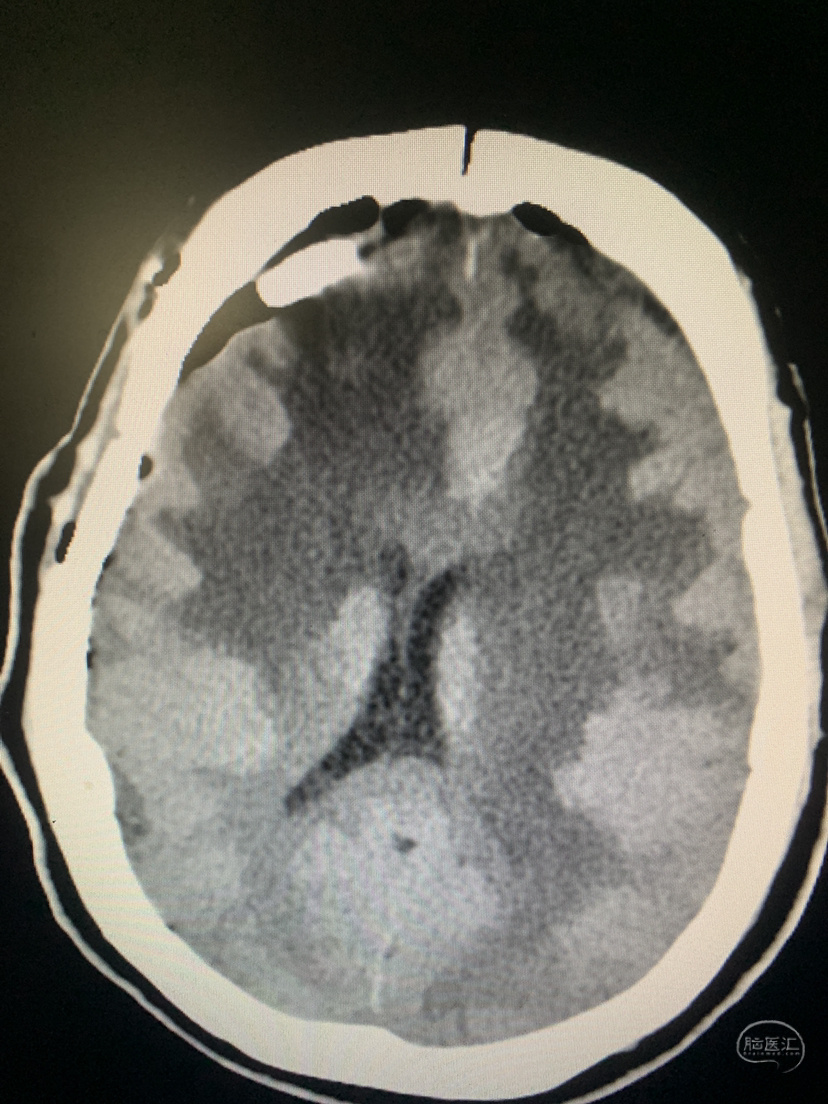

术前CT

术前CT